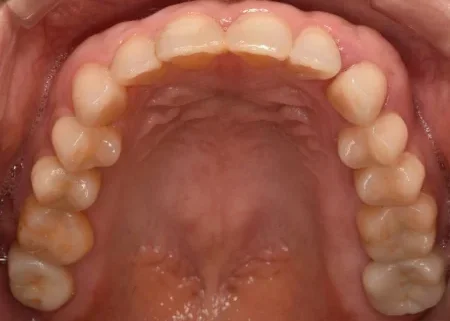

治療後

| 行ったご提案・治療内容 | 患者様のご要望通り、銀でできた詰め物と被せ物を全て取り外して、白い素材で作り直す治療の計画を立てました。 部分的な詰め物は、隣り合う歯の色味に合わせやすく自然な白さが特徴の素材である「セラミック」、被せ物はセラミックの中でも強度が高い「ジルコニア」で作製しました。 |

| 術後の経過・現在の様子 | 奥歯全体が白く美しくなり、お口を開けた時も自然で、患者様も大変満足されています。 メンテナンスに移行した現在も、月1回の頻度でクリーニングにご来院していただいています。 |